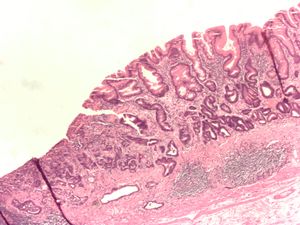

ـ التنطير الهضمي والخزعة: مع التطور الكبير في مجال صناعة المناظير الضوئية الليفية المرنة flexible fiberoptic endoscopes، صار من السهل إجراء فحص كامل ودقيق لمخاطية المعدة، ومشاهدة التغيرات المرضية، ومنها سرطان المعدة، مباشرة، وكذلك أخذ خزعات متعددة منها من أجل التشخيص النسيجي. ويجب أخذ 4 إلى 6 خزعات من أي آفة مشبوهة في المعدة لرفع دقة التشخيص.

يساعد التنظير الهضمي أيضاً على تحديد مكان الآفة في المعدة، ويمكن باستخدام التصوير بالأمواج فوق الصوتية خلال التنظير endoscopic ultrasound دراسة مدى ارتشاح الورم في جدار المعدة، ومن ثم التفريق بين سرطانات المعدة الباكرة والمتقدمة بدقة تصل إلى نحو 80%.